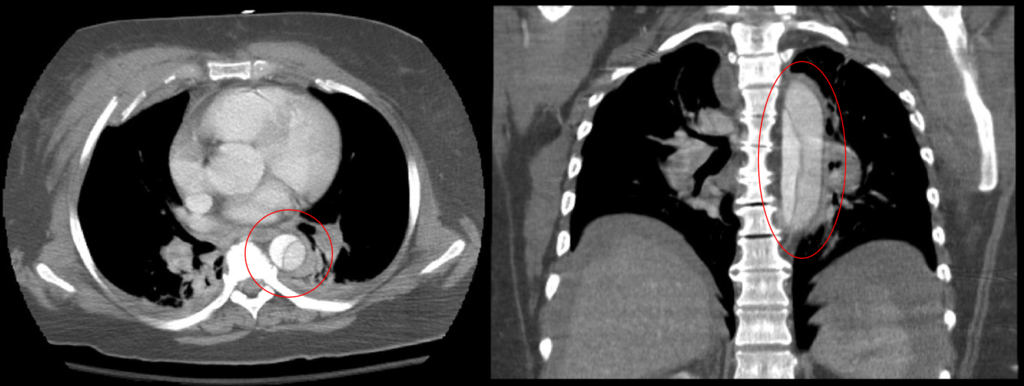

Aortic Dissection

Aortic dissection is caused by shearing force allowing blood leaking through the media of the aortic wall due to an intimal tear.

Aortic dissection occurs in the high-stress zone of the proximal portion of the aorta and is accompanied by medial weakening.

Risk factors of aortic dissection include:

- Hypertension in elderly persons, characterized by vasa vasorum hyaline arteriosclerosis

- Genetic connective tissue abnormalities in younger individuals such as Marfan syndrome or Ehlers-Danlos syndrome, characterized by weak connective tissue and cystic medial degeneration

The media sags as a result of decreased flow.

Weakness of the connective tissue in the media is a characteristic symptom of Marfan syndrome and Ehlers-Danlos syndrome (cystic medial necrosis).

Symptoms of aortic dissection include:

- Intense chest pain

- Chest pain that radiates to the back

Complications of aortic dissection include:

- Death secondary to cardiac tamponade (the most common)

- Rupture with lethal hemorrhage

- Obstruction of branching arteries (such as the coronary or renal arteries)

- End-organ ischemia